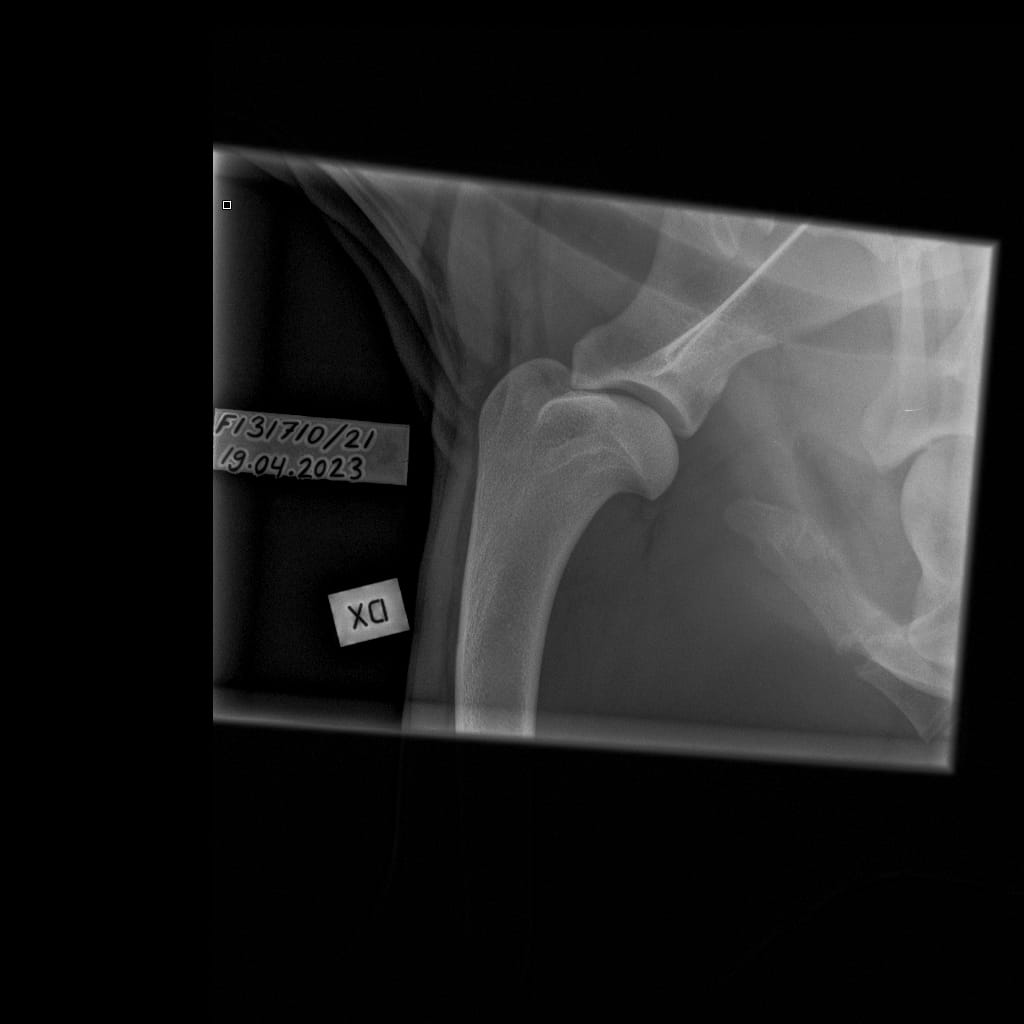

| Shoulders: | Unaffected/unaffected | ||

| Shoulders: | Unaffected/Unaffected |

| Shoulders: | Unaffected/Unaffected | |

| Shoulders: | Unaffected/Open to interpretation |